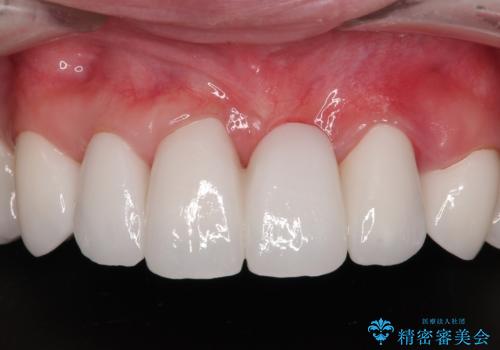

自他共に認める、非常に色白の患者様であったため、黄ばんだ歯の色を白くすることを希望されており、歯周病治療の該当部位に限らず、全顎的にオールセラミッククラウンにて補綴治療を行うこととしました。

多くの外科処置を行ったため、治療期間も長くなり、患者様の負担は非常に大きなものとなりましたが、明るく健康的な口元となり、患者様には大変満足していただけました。